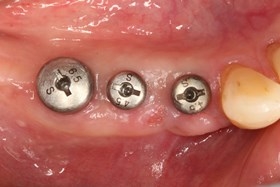

植牙後癒合狀況良好

假牙完成照

因植牙恢復正常咬合